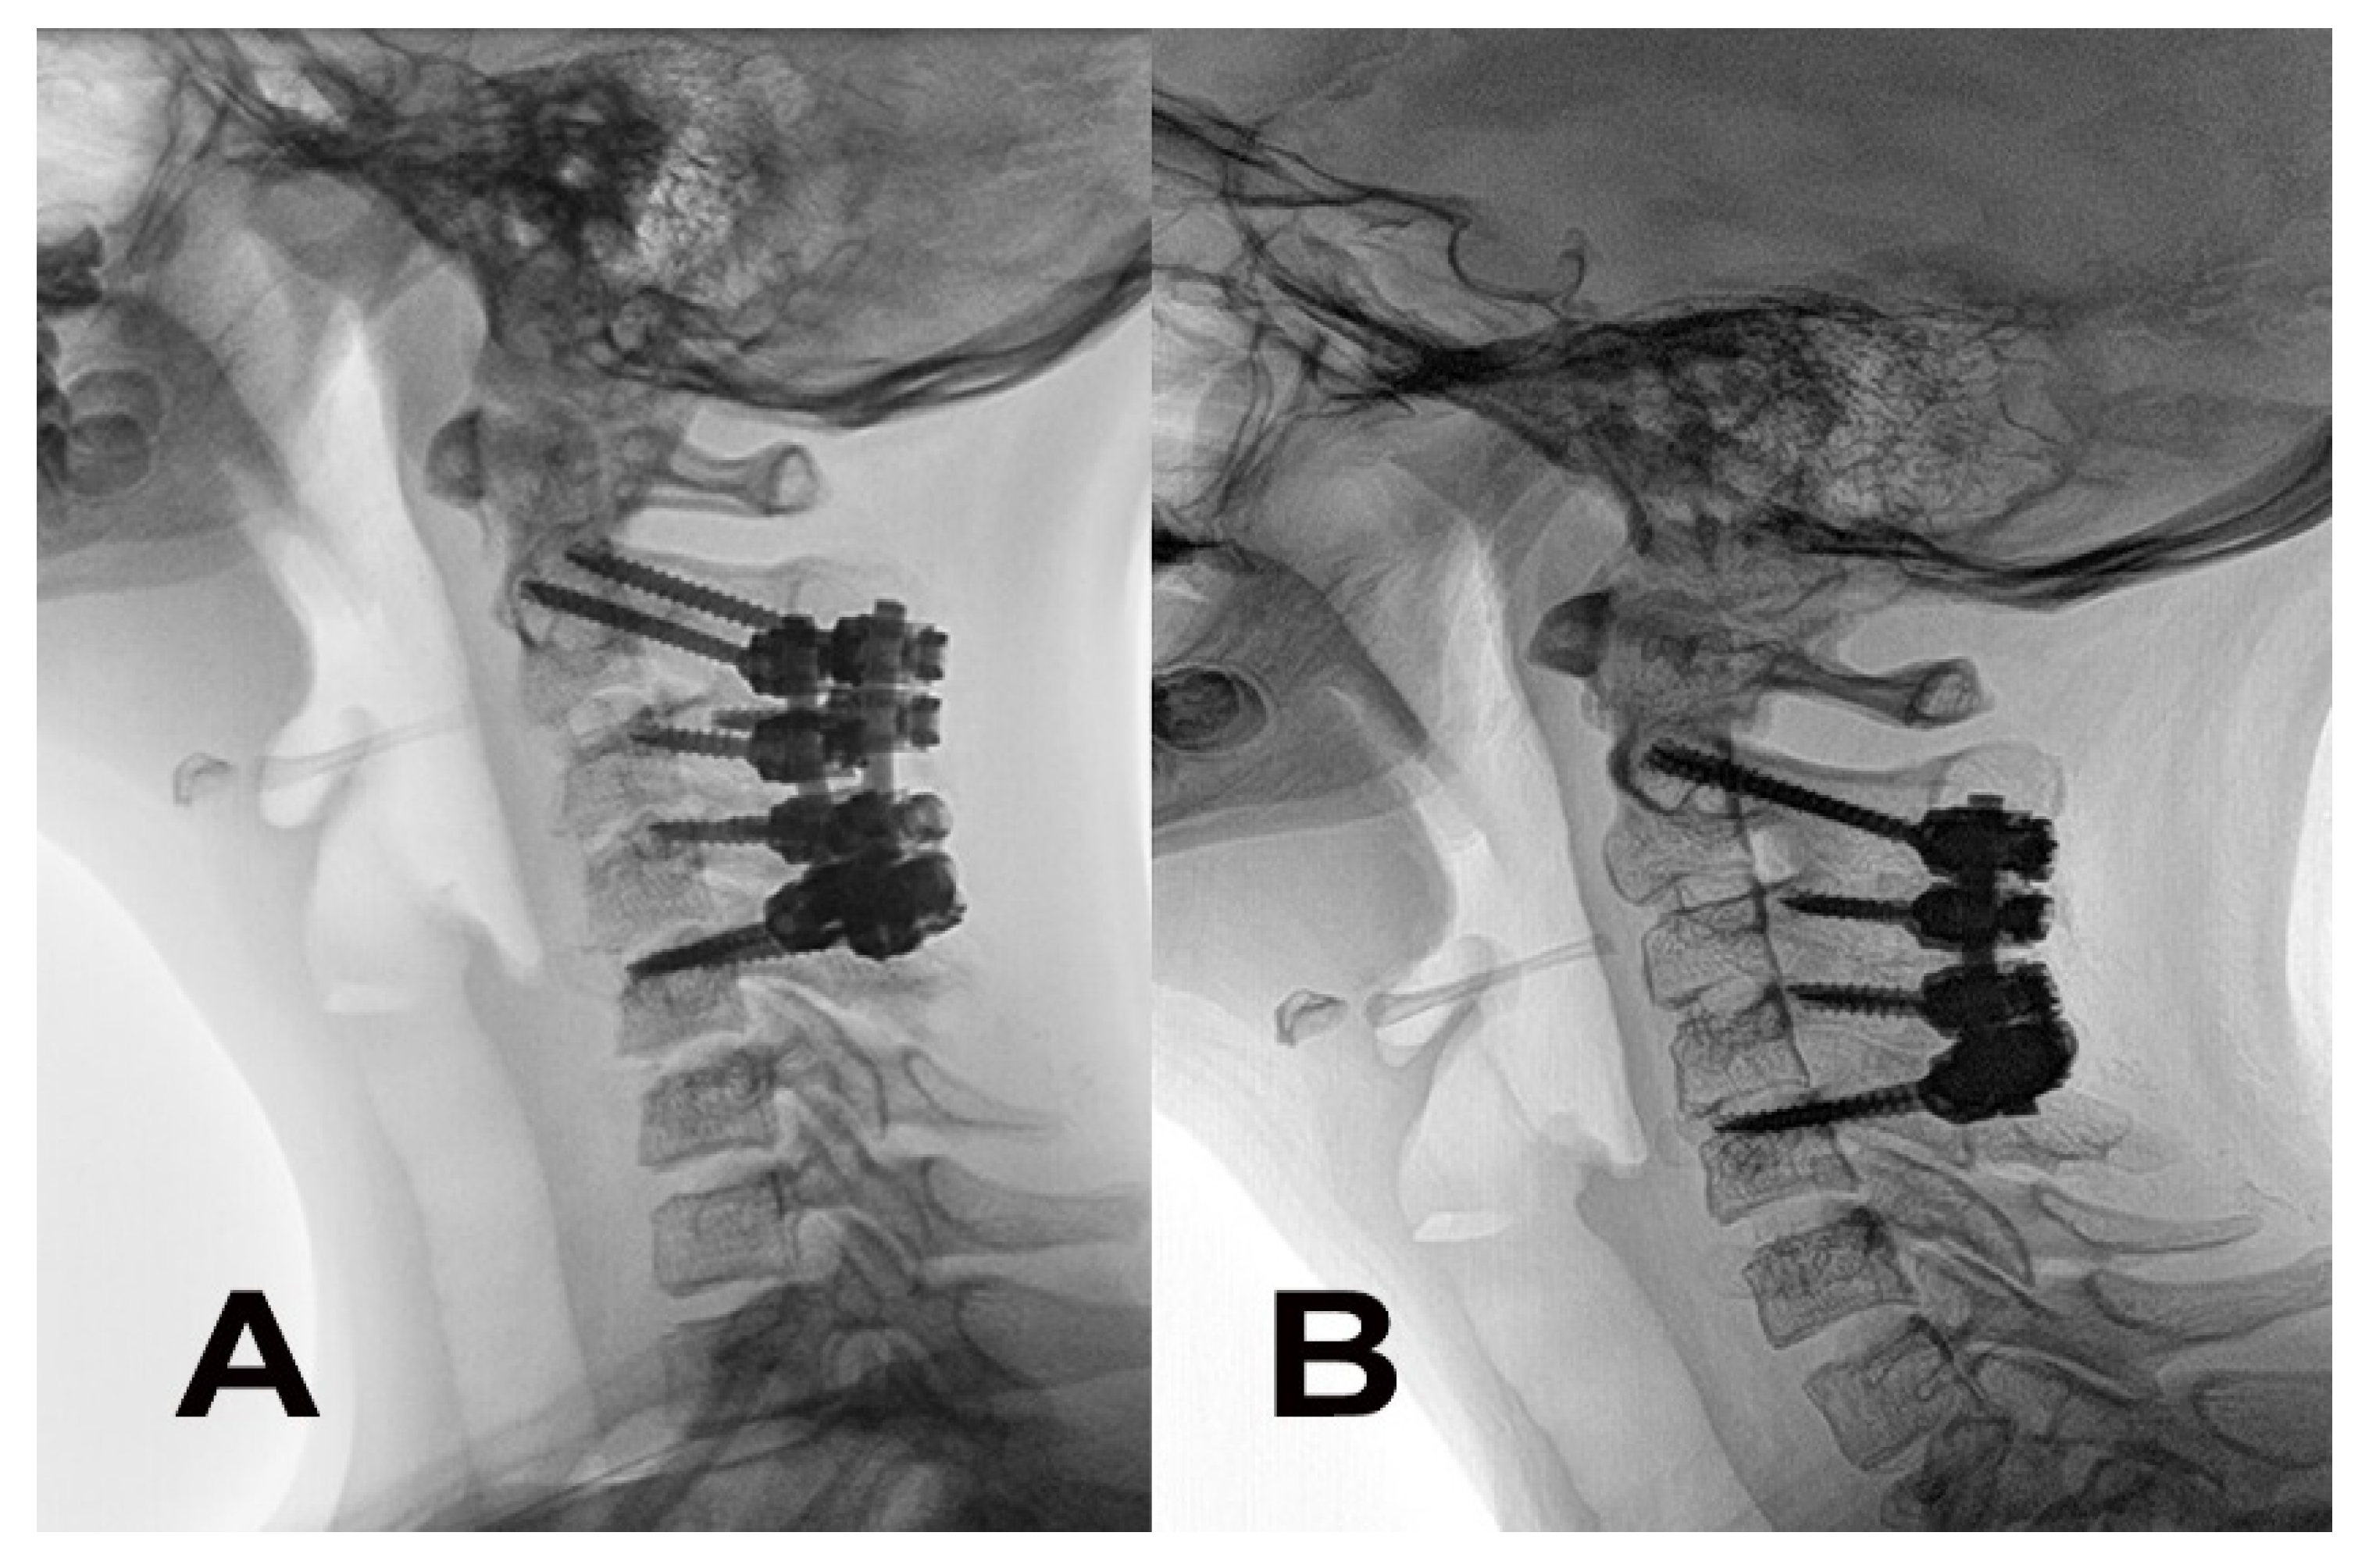

2. Case Report